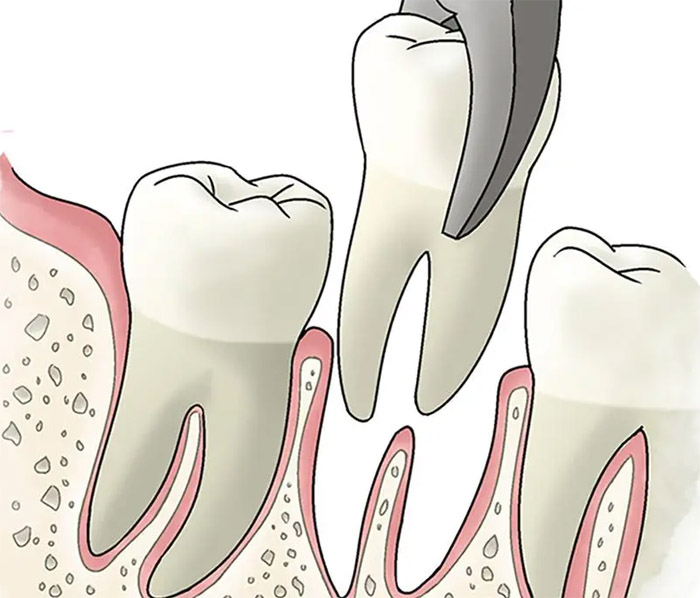

Extractions

Consulter son chirurgien Dentiste, Je suis contre les extractions, sauf en cas de force majeure.

Ma vocation est de sauver vos dents